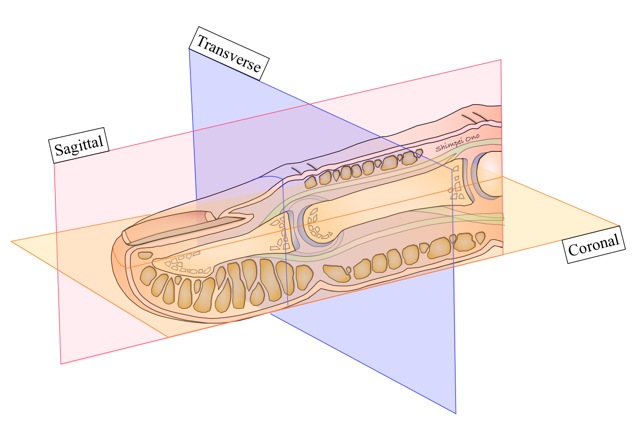

矢状面、冠状面、水平面が分からない? これで完全理解!! 身体の方向をあらわす3つの基準面 矢状面、冠状面、水平面 、本当に理解している?ここって、結構間違えやすい部分だよね。 なので、今回は「矢状面 正中面 」「冠状面」「水平面」のそれぞれの覚え方を。

身体の方向をあらわす3つの基準面 矢状面 正中面 、冠状面、水平面 のイラスト🎨 フリー素材 看護roo! カンゴルー。

矢状面、冠状面、水平面が分からない? これで完全理解!! 身体の方向をあらわす3つの基準面 矢状面、冠状面、水平面 、本当に理解している?ここって、結構間違えやすい部分だよね。 なので、今回は「矢状面 正中面 」「冠状面」「水平面」のそれぞれの覚え方を。

身体の方向をあらわす3つの基準面 矢状面 正中面 、冠状面、水平面 のイラスト🎨 フリー素材 看護roo! カンゴルー。

人体の基準面で矢状面 と 冠状面 がごっちゃになる人へ。 このイラストのイメージがあると記憶に残ります。

矢状面、冠状面、水平面が分からない? これで完全理解!! 身体の方向をあらわす3つの基準面 矢状面、冠状面、水平面 、本当に理解している?ここって、結構間違えやすい部分だよね。 なので、今回は「矢状面 正中面 」「冠状面」「水平面」のそれぞれの覚え方を。

矢状面、冠状面、水平面が分からない? これで完全理解!! 身体の方向をあらわす3つの基準面 矢状面、冠状面、水平面 、本当に理解している?ここって、結構間違えやすい部分だよね。 なので、今回は「矢状面 正中面 」「冠状面」「水平面」のそれぞれの覚え方を。

horizontal sagittal and coronal planes水平面,矢状面,冠状面 _sigittal coronalhorizontal之间的区别-CSDN博客。

DENTALISH歯科英語チャンネル🦷 ▶︎Anatomical plane 解剖学的平面CTなどでよく見かける三次元平面に関してです! ↔️体を左右に分ける面 矢状面:Sagittal plane 縦断面:Longitudinalplane ↕️体を上下に分ける面 軸断面:Axial planeInstagram。

人体の3つの基準面 矢状面・冠状面・水平面.組織細胞ゴロー .体のしくみ医療系学生の勉強垢看護学生の勉強垢鍼灸科理学療法学科作業療法士の勉強垢解剖生理学ノート解剖学講座生理学ノート国試過去問柔整科歯科衛生学生ナース。

分清frontal plane 额状面 、coronal plane 冠状面 、transverse plane 横断面 、sagittalplane 矢状面 -CSDN博客。